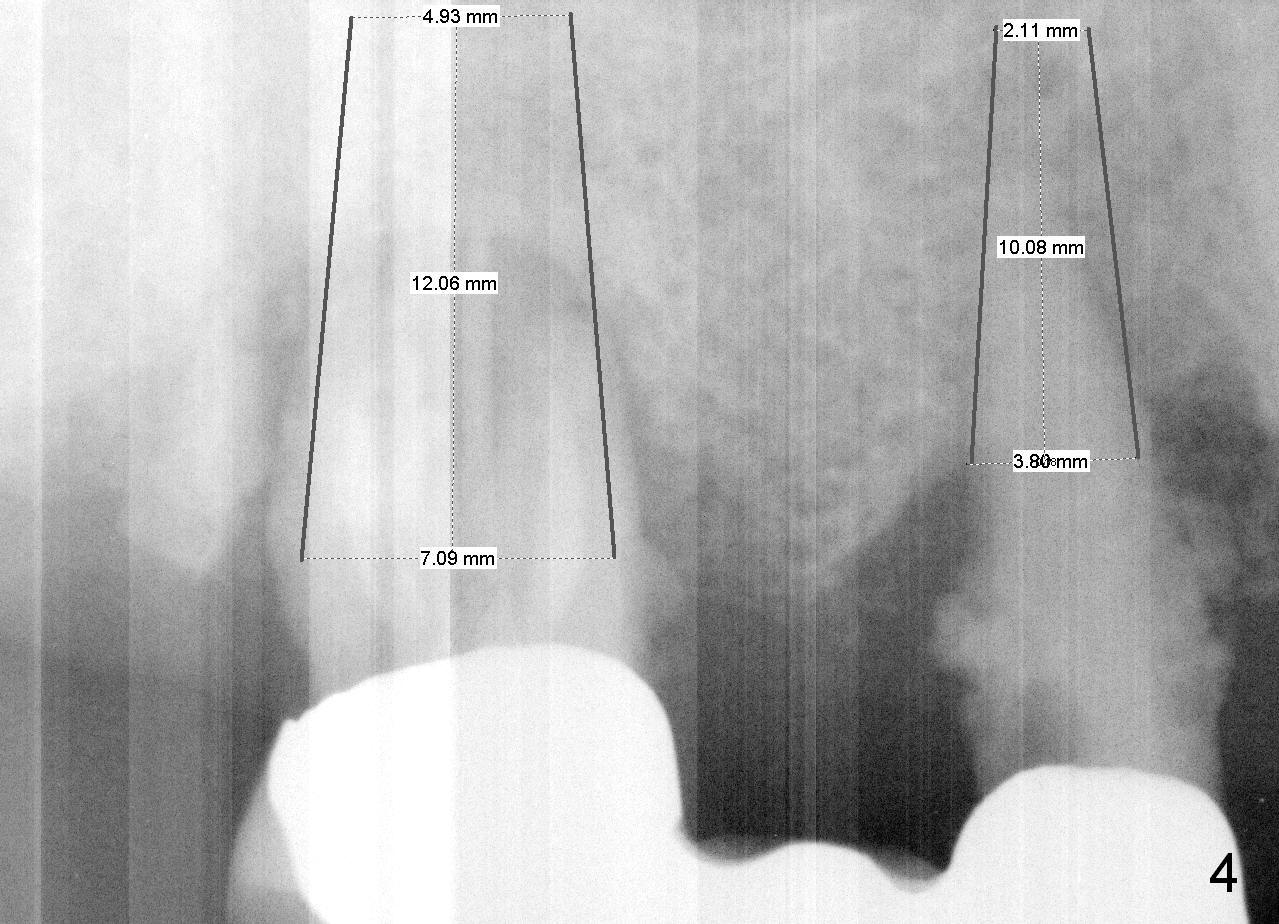

A 78-year-old lady (YT) has had poor dentition.  The tooth #2 fractured 3 years ago (Fig.1).  Now bone loss around the abutments for the bridge at #3-5 is more severe (Fig.2).  There is an abscess palatal to the tooth #5.  After extraction, the socket at #3 should be large (treated with 2% Xylocaine/1:50,000 Epinephrine).  An extra wide implant is expected.  Since there is more than 12 mm of bone in height (Fig.3), a UF implant is the most appropriate (6, 6.5 or 7x12 mm, Fig.4).  The longest extra wide SM implant is 10 mm.